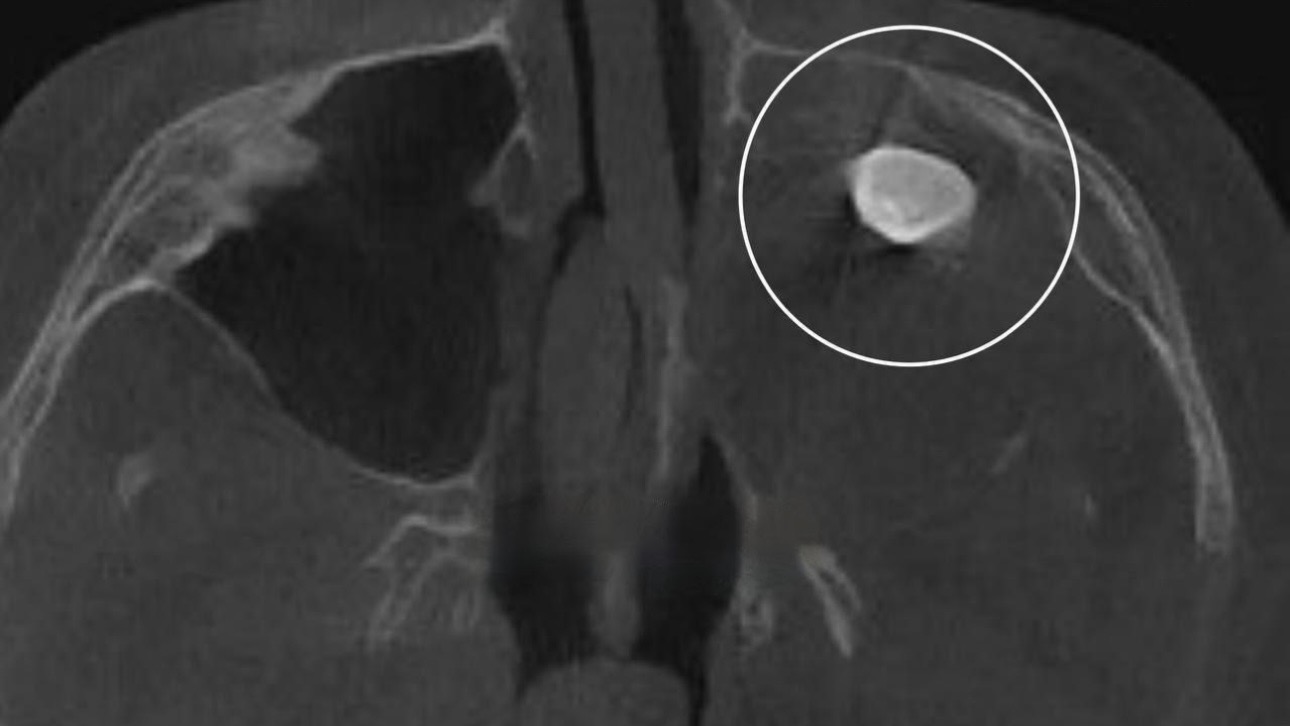

Фото: Московская медицина

15-летний подросток из Москвы обратился к врачам с жалобами на заложенность носа и асимметрию лица. При обследовании у него в гайморовой пазухе обнаружили зуб, ребенку поставили диагноз — тератома. Насколько эта болезнь опасна и по каким признакам ее можно распознать, выясняла «Вечерняя Москва».

В 2024 году в Подмосковье произошли похожие случаи. Тератому выявили у двух женщин. У одной из них — 34-летней жительницы Подольска — диагностировали кисту с волосами и зачатками костей черепа в правом яичнике. Второй случай зафиксировали у 17-летней девушки — ей удалили огромную опухоль-тератому весом более семи килограммов, которая на 80 процентов состояла из зачатков мозговой ткани, хрящей, костей, а также жировой, мышечной и незрелой эмбриональной ткани.

Как рассказал пластический хирург Игорь Короткий, тератома — это злокачественное новообразование, которое может появиться в области лица, зубного ряда и копчика.

— Причем в области копчика, у ягодичной складки, также возможно появление зубов или волос, — уточнил врач.